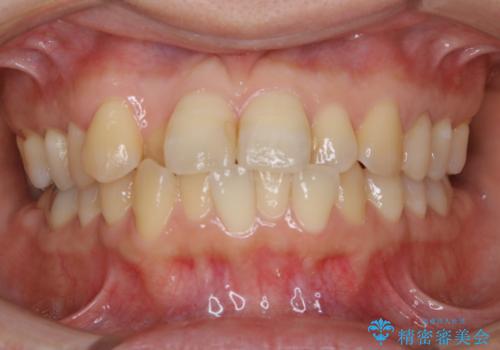

ガタガタの度合いが強く、上下の前歯が当たっていない状態であったので、治療期間が少し長くなりました。しかし、ガタガタがなくなり、前歯で食べ物が咬み切れるようになり、患者様にも満足していただけました。